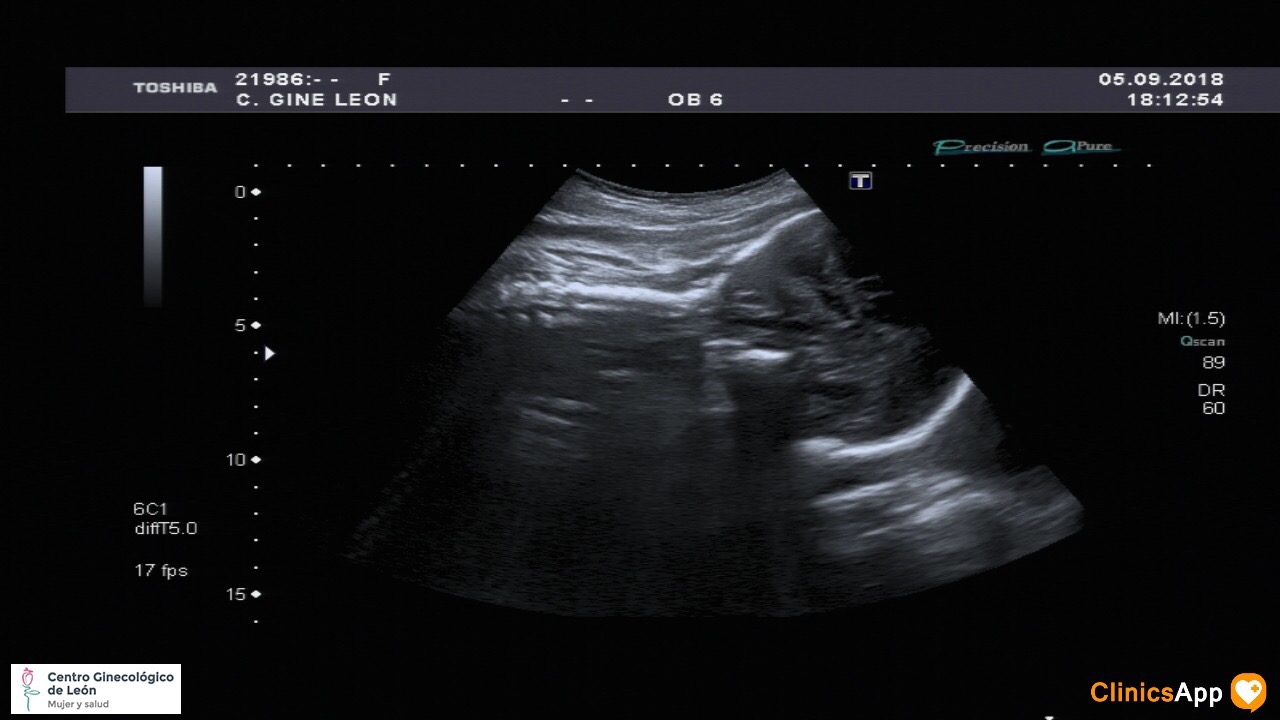

Nueva ecografía de la hermana de Mateo Nueva ecografía… y aún sin nombre. Ya pesa más de 2Kg, así que empieza a estar más apretada. Fecha publicación 05/09/2018 Publicada por papá Publicada en Fotos, Galerías, Prenatal Comentarios 0 Entrada anterior: Con mamá al parque Entrada siguiente: Caco balí n° 23 Deja una respuesta Cancelar la respuestaComentario * Nombre * Correo electrónico * Web Guarda mi nombre, correo electrónico y web en este navegador para la próxima vez que comente. Recibir un correo electrónico con los siguientes comentarios a esta entrada. Δ